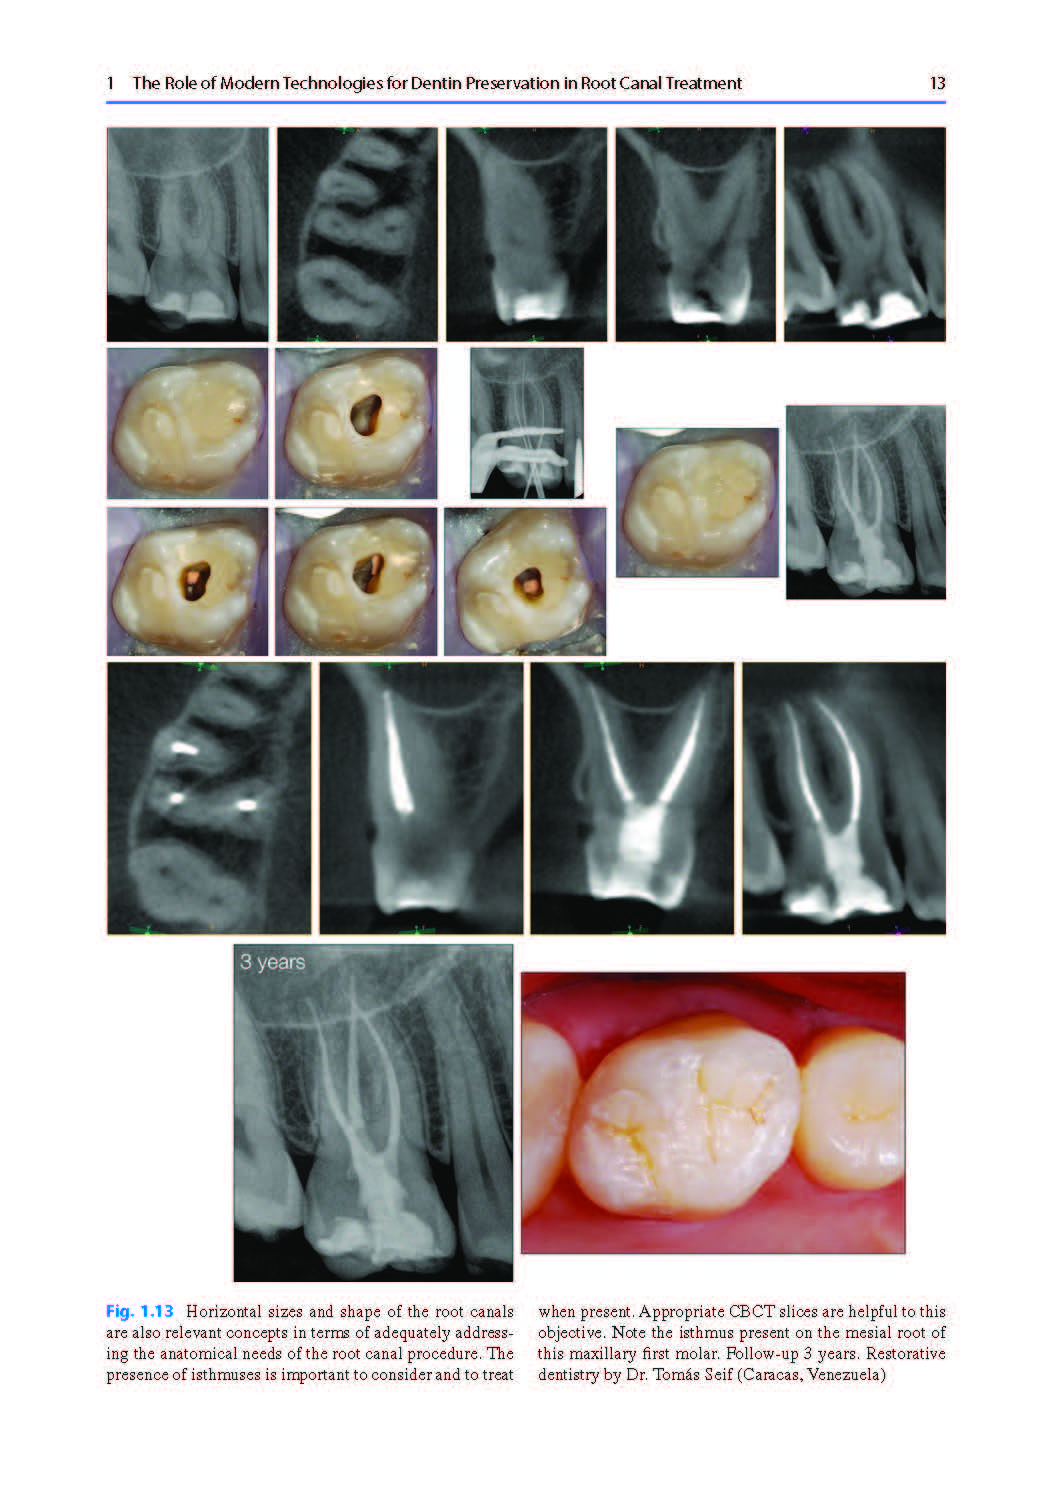

A central principle emphasized by the author is the primacy of anatomy. Every endodontic procedure must be guided by anatomical knowledge to achieve predictable and long-lasting results. Therefore, the term “minimally invasive” is redefined as “anatomically guided”, leading the author to propose the concept of “Anatomically Invasive Endodontics.”